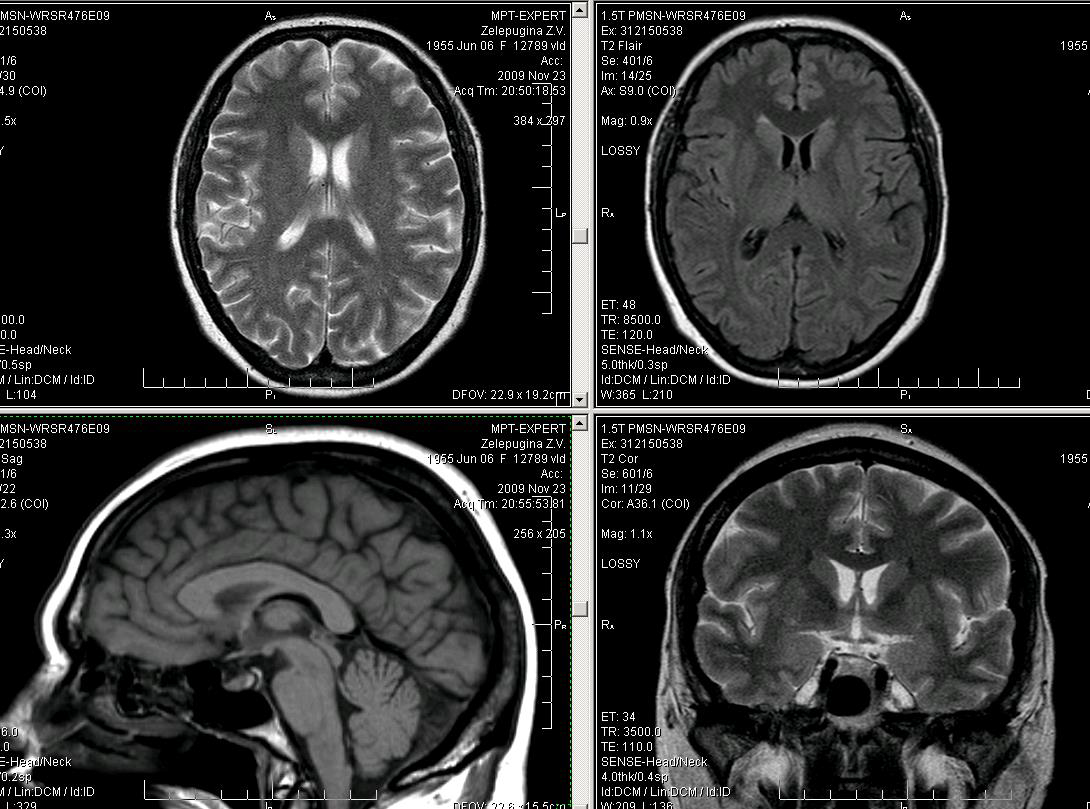

Достоинства МРТ – полипроекционность, высокая межтканевая контрастность и высокая разрешающая способность

МРТ. Локальный участок утолщения и полимикрогирии правой лобной доли с наличием структурных изменений серого вещества (Flair). На РКТ не дифференцируется.